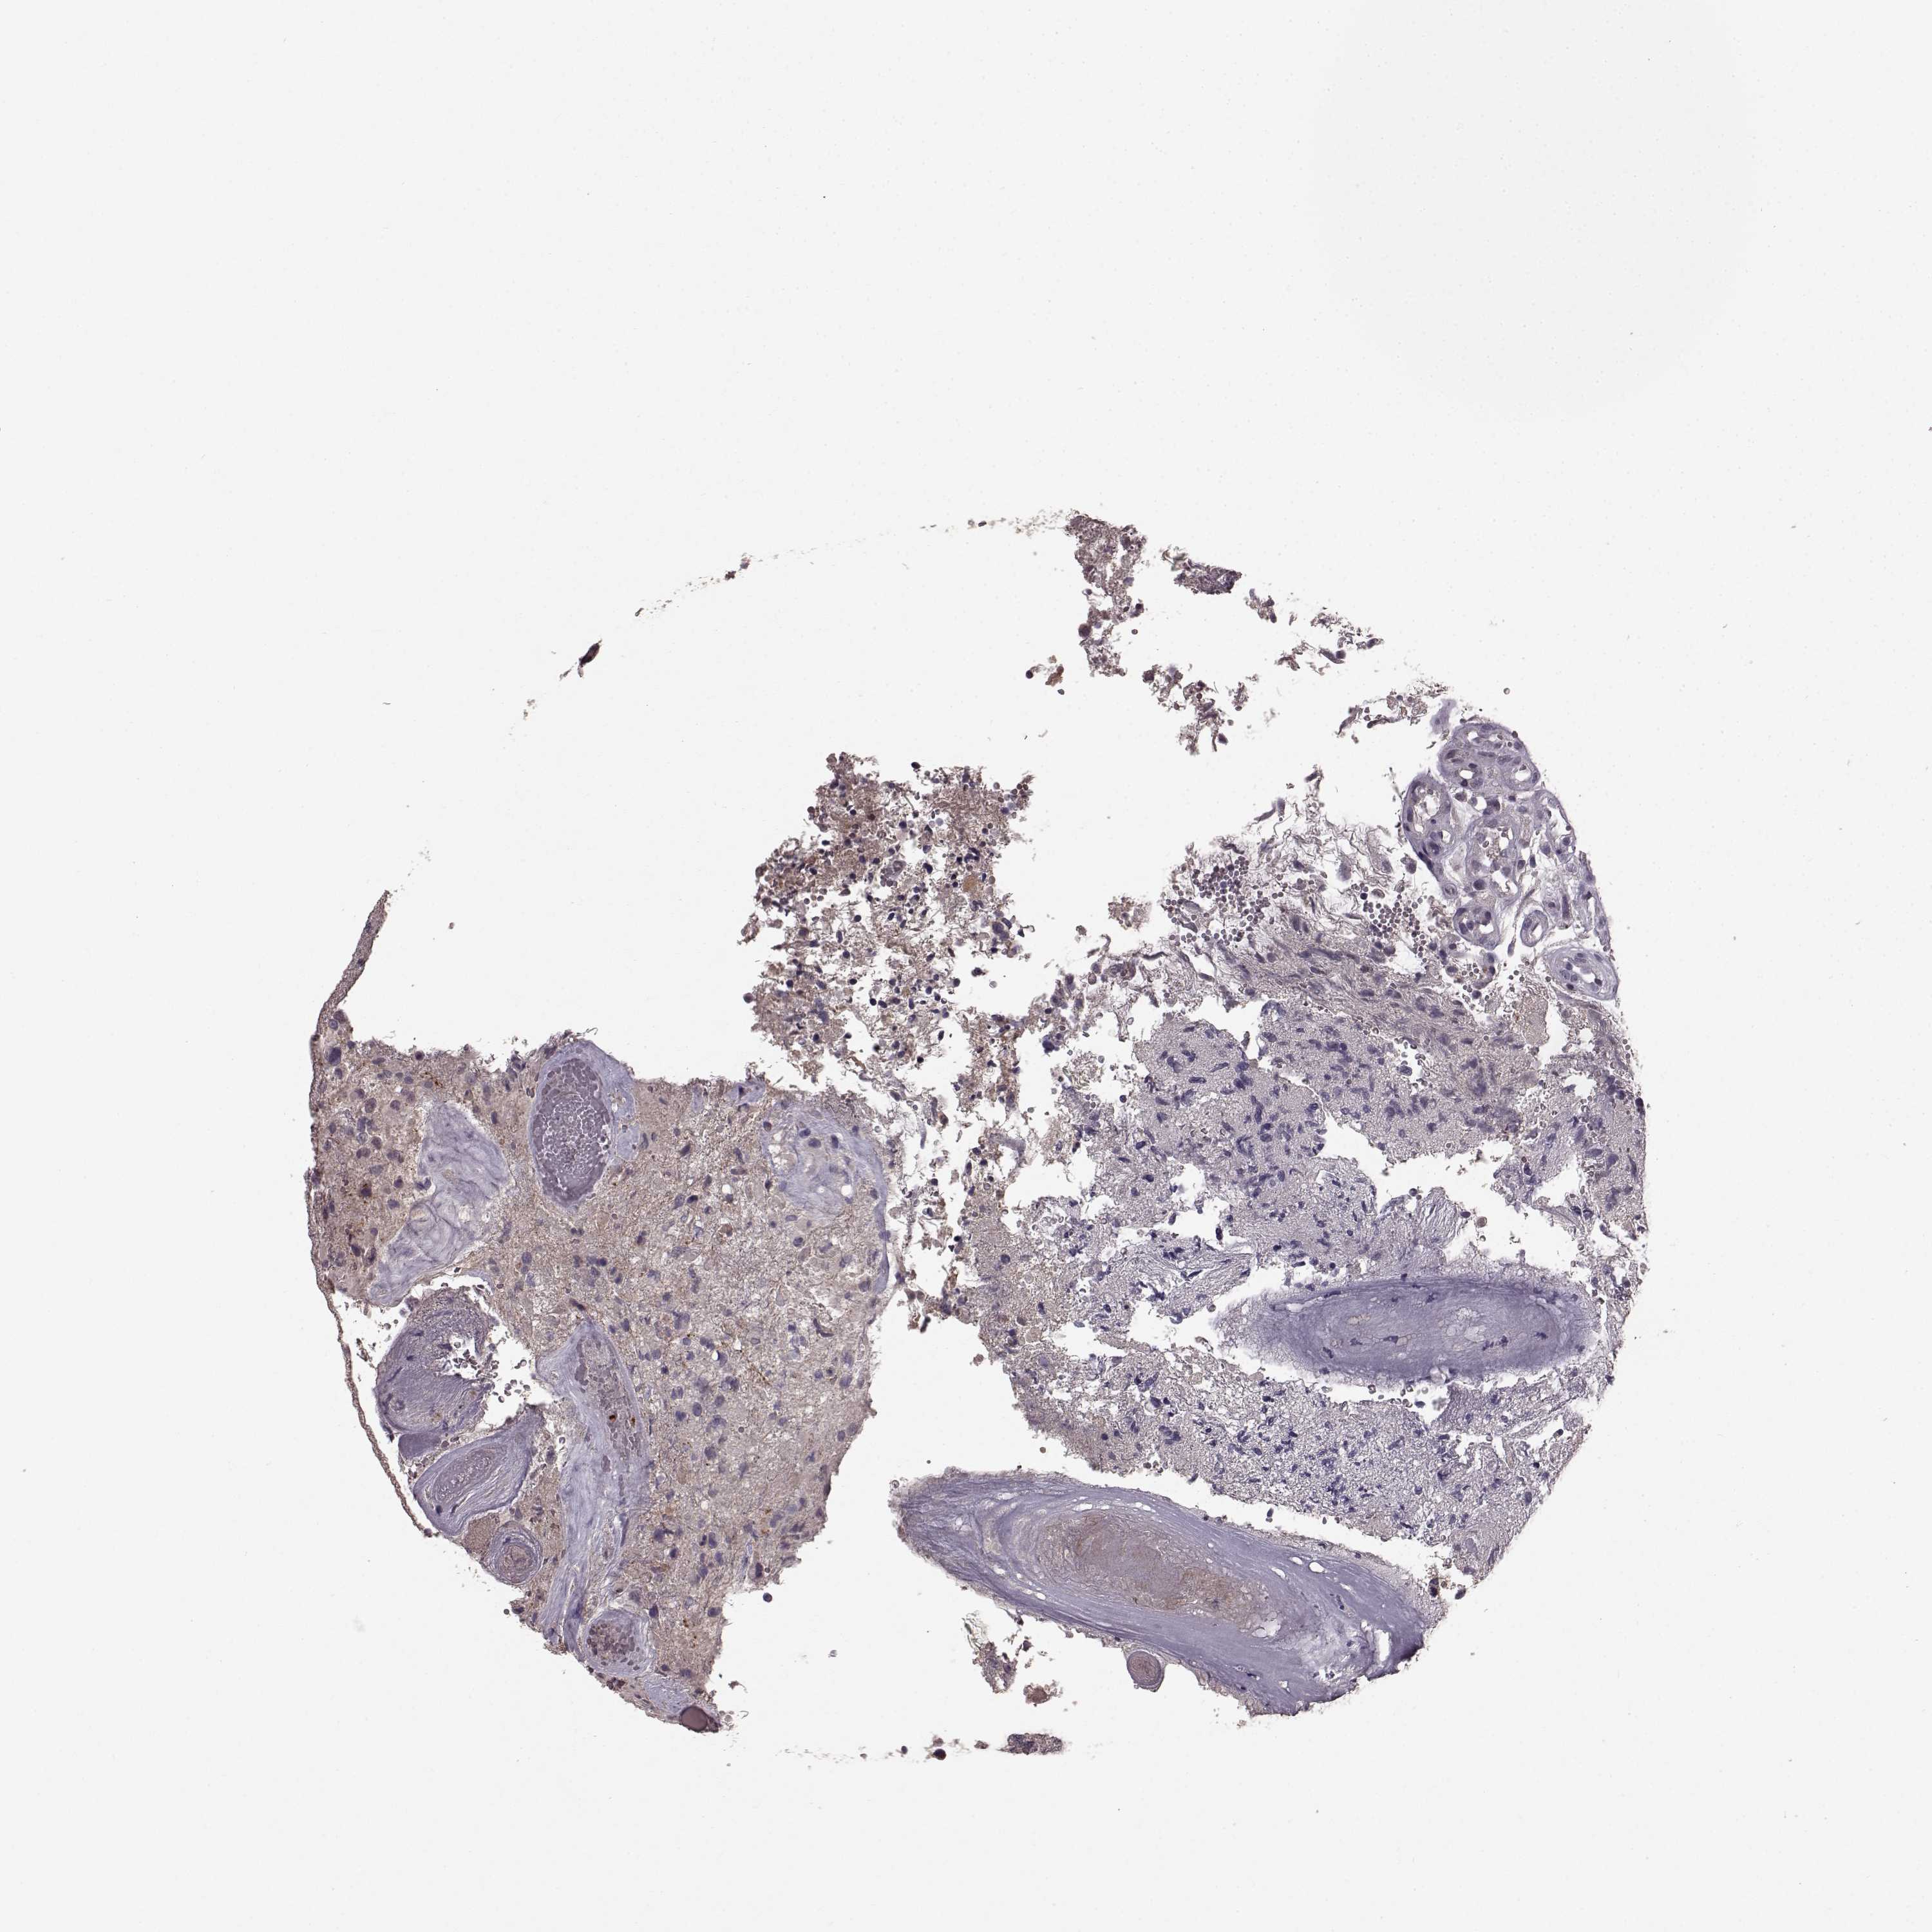

GLIOMA - Protein expressioni

A mouse-over function shows sample information and annotation data. Click on an image to view it in a full screen mode. Samples can be filtered based on level of antibody staining by selecting one or several of the following categories: high, medium, low and not detected. The assay and annotation is described here.

Note that samples used for immunohistochemistry by the Human Protein Atlas do not correspond to samples in the TCGA dataset.

Antibody stainingi

Antibody staining in the annotated cell types in the current human tissue is reported as not detected, low, medium, or high, based on conventional immunohistochemistry profiling in selected tissues. This score is based on the combination of the staining intensity and fraction of stained cells.

Each image is clickable and will lead to virtual microscopy that enables deeper exploration of all samples and also displays staining intensity scores, fraction scores and subcellular localization as well as patient and tissue information for each sample.

Antibody HPA067812

Antibody HPA071461

Staining

High

Medium

Low

Not detected

Intensity

Strong

Moderate

Weak

Negative

Quantity

>75%

75%-25%

<25%

None

Location

Nuclear

Cytoplasmic/membranous

Cytoplasmic/membranous,nuclear

Glioma, malignant, Low grade

Glioma, malignant, High grade